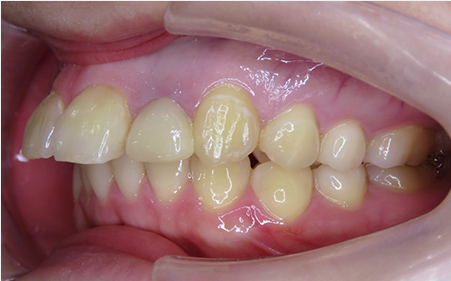

CASE08

Before

After

| 施術名 |

インビザラインコンプリヘンシブを用いた矯正治療(叢生) |

| 治療期間 |

1年 |

| 治療費 |

880,000円(税込) |

| リスク |

マウスピース装置により疼痛・咬合時痛を生じる事があります。割れたり壊れたりする事があります。 |

歯科医師からのコメント

「上顎八重歯が気になる」で来院されました。分析すると、軽度なねじれでしたのでインビザラインGoにて治療をすすめていきました。マウスピースを積極的に使用し、順調に治療がすすんでいきました。仕上がりにとても満足しておられました。